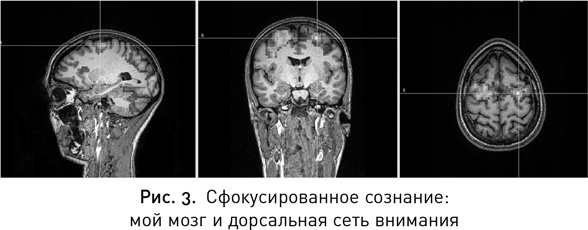

Мы направляемся в комнату с большим креслом — теперь в ней появился просто необъятных размеров монитор. Мой мозг (рис. 3). Не знаю, чего именно я ожидала, но выглядит он вполне нормально; все нужные бугры на месте, никаких дыр нигде нет. Майк перекрыл место расположения дорсальной сети внимания снимком моего мозга и отметил цель на зоне сети, которая называется фронтальным глазным полем, — сюда и будет нацелена стимуляция.

Иллюстрация к книге — Мой продуктивный мозг. Как я проверила на себе лучшие методики саморазвития и что из этого вышло [i_004.jpg]